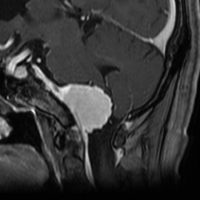

大脳鎌テント接合部髄膜腫 falcotentorial meningioma

30代の女性に発生した髄膜腫です,一見すると松果体細胞腫と見分けはつきません。右の画像に見られるように典型的な中脳水道狭窄を生じていました。

軽度の閉塞性水頭症もありますが,頭痛も無く無症状なので経過を観察しました。髄膜腫だと診断できるのは,右の画像で見られるようにガレン大静脈が右側に偏っているからです。松果体細胞腫の場合は,ガレン大静脈は上方に変位します。

1年間経過観察したら水頭症が進行して脳室が拡大,腫瘍のサイズも大きくなりました。右側の画像で見られるようにガレン大静脈の左側のテントの下面から発生した髄膜腫でした。

左は手術直後の画像です,手術は左側のテント下面を見るために,後頭部経テント法 OTA occipital transtentorial approach で,小脳テントの左側を切断して腫瘍を全摘出しました。右側は6年後の画像ですが,腫瘍再発はありません。

「注意」症状のない患者さんには,なかなか勧められないリスクの高い手術です。この患者さんの場合は無症状で水頭症も軽度で経過観察をしたのですが,本当はそうしてはならないものでした。閉塞性水頭症が急激に悪化して,急性水頭症のために意識障害になる可能性があるものです。